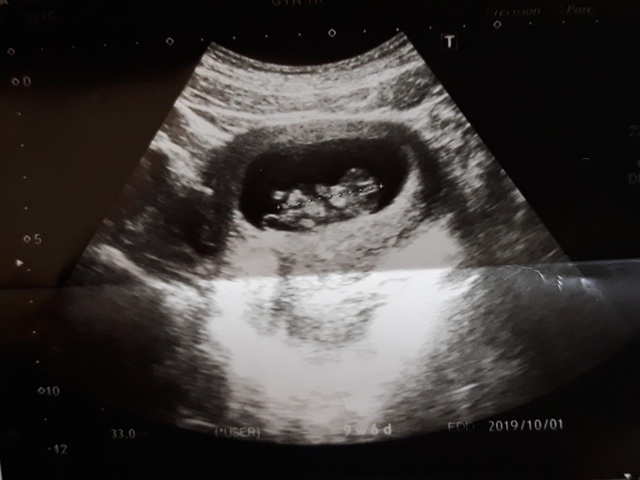

當小純進入診間看診時,我並沒有進去,因為小純說,有時男生不能進去,會被請出來。在外頭等待的我感到很緊張,不久之後,謢理人員請我進入診間,我嚇了一跳,想說發生什麼事了,進入之後,得知小純真的懷孕了,而且已懷了九星期又五天。看診的醫師說,驗孕棒第二條線淡淡的,沒想到胚胎照出來那麼大了,說Baby很健康。還說一閃一閃的是他的心跳,有頭、有手、有腳還有臍帶。小純後來說看了內心覺得很感動,才叫我一起進去看。

小純肚子裡的Baby超音波圖↓